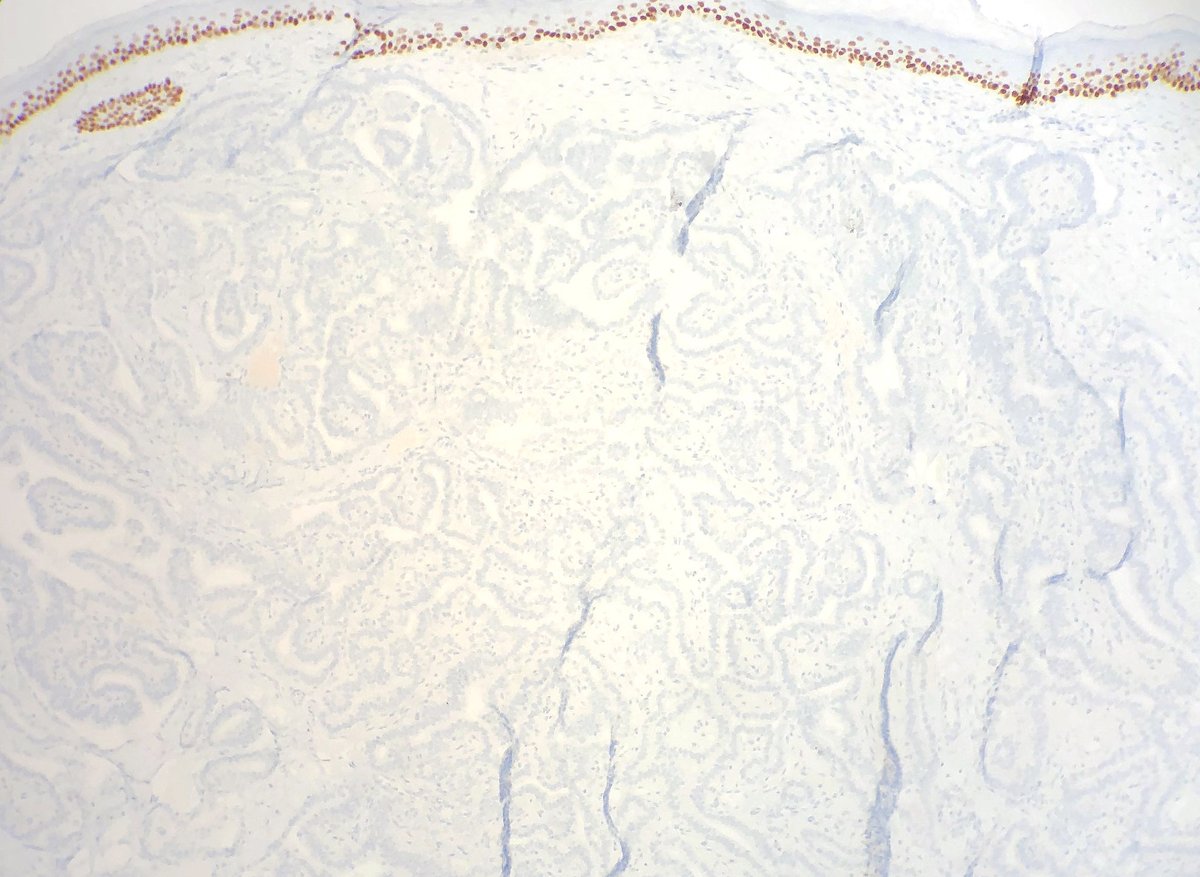

Unaware, you made a simple Dx that pinned down the patient syndrome… 💁‍♂️💅🏻🦄 Who am I? What syndrome am I pointing to? #DermPath #PediPath #PathResidents Not #TooCloseToDiagnose

Unaware, you made a simple Dx that pinned down the patient syndrome… 💁‍♂️💅🏻🦄

Who am I? What syndrome am I pointing to?